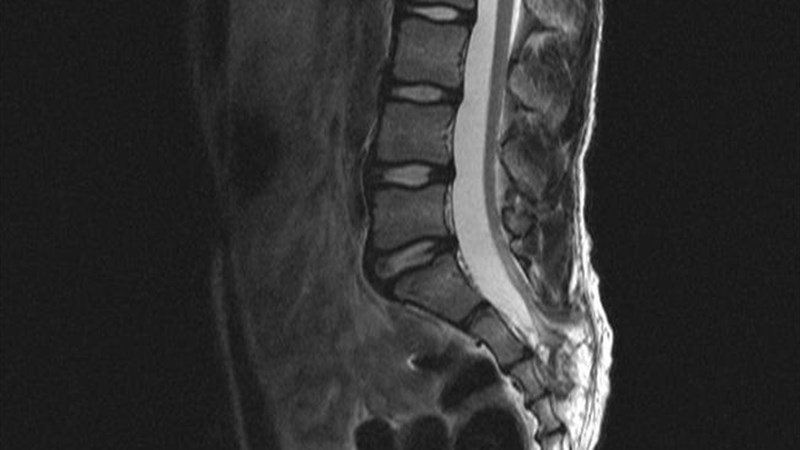

Синдром фиксированного спинного

Синдром фиксированного спинного 114 фото